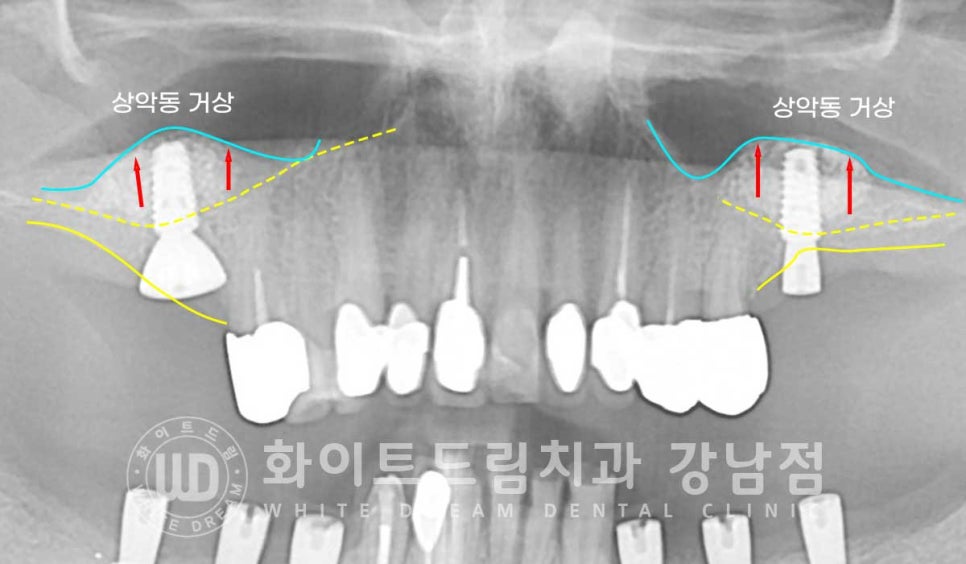

환자분의 상악동 거상 술 전의 잇몸뼈 높이와 거상 후를 비교해 보면

한눈에 어떤 부위에 대량의 뼈이식이 진행됐는지 확인하실 수 있을 겁니다.

노란색 점선이 초기 환자분의 잇몸뼈 높이이며, 거상 후 하늘색 선 만큼 상악동이 올라갔고

그 사이에 하얗게 보이는 뼈이식재가 들어간 것이 확인됩니다.